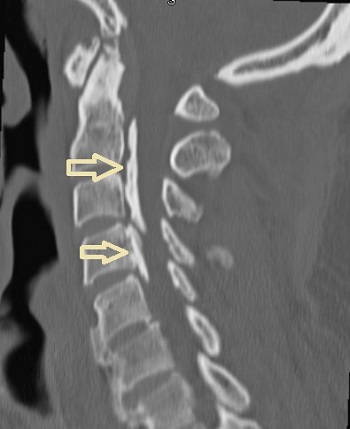

後縦靱帯骨化症(ossification of posterior longitudinal ligament:OPLL)とは、脊椎後縦靱帯が骨化し、脊髄と脊髄神経根を圧迫、感覚障害や運動障害を呈する病気です。後縦靱帯骨化症(OPLL)は男性に多く、その原因は不明ですが、遺伝的素因、性ホルモン異常、副甲状腺の病気やカルシウム・ビタミンDの代謝異常、糖尿病、肥満等が関与するとされます。

後縦靱帯骨化症(OPLL)の手術治療は、

- 頸の後方から除圧する

- 骨化した後縦靱帯を、頸の前方から椎体ごと除去し、間隙に腸骨を自家移植します

副甲状腺機能低下症では、大脳基底核の石灰化などの異所性石灰化(異所性骨化)が起こりますが、頚椎後縦靱帯骨化症(OPLL)などの脊柱靱帯骨化症の発症にも関与すると考えられます。(日骨代謝会誌 1986;3(3〜4):151-160)